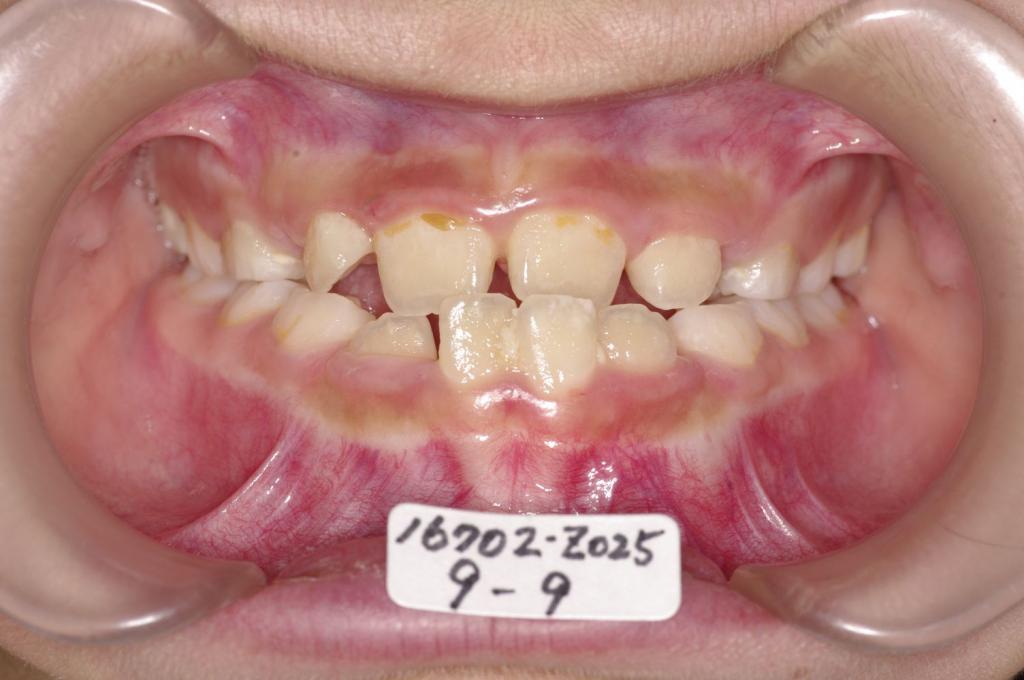

子供の矯正治療

(治療期間、治療前後写真、治療方法、費用)WORKS

下記の実績データをクリックして頂くと「性別」、「治療開始年齢」、「治療終了年齢」、「治療方法(矯正治療装置写真含む)」、「治療終了までの費用」など、詳細な矯正治療データをご覧頂けます。